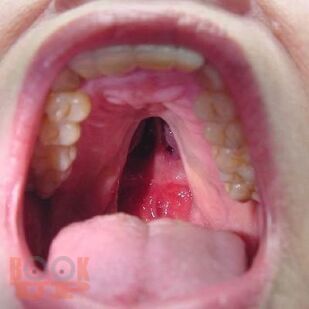

Данное пособие содержит материал, отражающий современные данные о лечебно-диагностических концепциях основных врождённых и приобретённых хирургических заболеваниях детского возраста. В пособии раскрыты ключевые позиции, этиологии, патогенеза, классификации, клинических проявлений, диагностики, консервативного и хирургического лечения, возможных осложнений и исходов хирургических заболеваний у детей. Сделан акцент на эмбриопатогенез и пренатальную диагностику врождённых аномалий развития у детей. Пособие содержит перечень вопросов для самоконтроля, тестовые задания и ситуационные задачи.